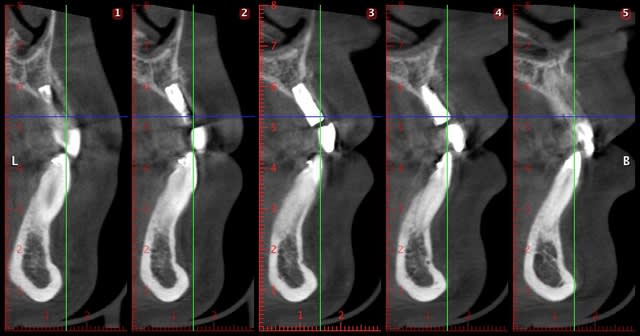

implant posé en 12 (agénésie) il y a 4 mois, le cbct montrait environ 4,4 mm en VP j'ai donc posé un 3,3/10 Zimmer (pas en TSV, qui commence à 3,7 de diamètre mais en SV)

ci joint les radio : le jour de la pose : os autour de l'implant, et cbct préop et .... radio et cbct à 4 mois...

Sachant qu'il faut laisser au moins 2 mm en vestibulaire...le compte n'y est pas...il fallait obligatoirement une technique d'augmentation osseuse ( rog par ex)..

Entre implant et dents adjacentes, il y a (a vue de nez) trop peu de distance, donc pas de vascularisation correcte de cet os : j'aurais choisi plus fin (monobloc a priori).

l'erreur a été surtout de poser pendant le traitement orthodontique, l'os au niveau de l'espace créé était beaucoup trop jeune. La perte osseuse va vraiment être difficile à rattraper ici.

Là, avec ma jeune expérience, si l'ortho dit que ce n'est pas fini, je ne cède pas à la patiente "impatiente", l'implant en bicortical ici est risqué étant donné l'épaisseur vestibulaire résiduelle.

De plus le traitement ortho étant en cours le remaniement était probablement en cours enfin ça dépend du stade du traitement...